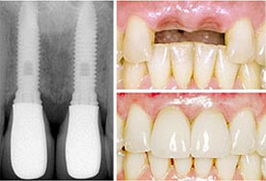

人工种植牙图片